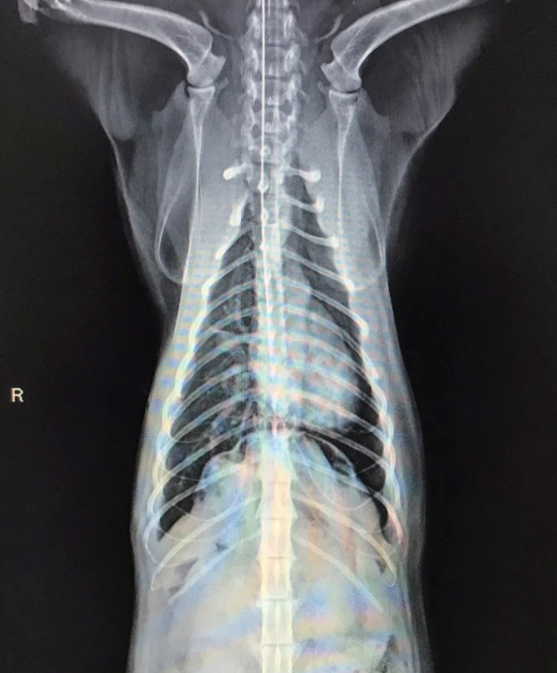

X光下,橫膈分界消失,左側胸腔有不正常軟組織影像

手術後X光,胸腔內異常軟組織影像已經消失

橫膈的邊緣又出現,胸腹腔有完整分界